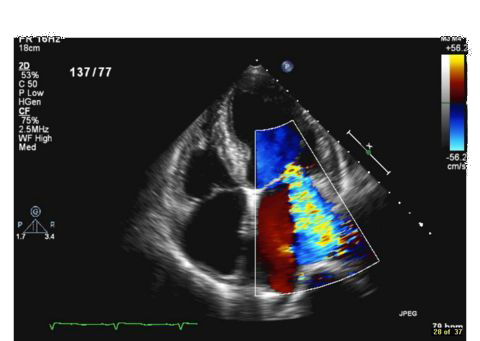

Ανεπάρκεια Μιτροειδούς Βαλβίδας

Η μιτροειδής βαλβίδα φράσσει το αριστερό κολποκοιλιακό στόμιο. Η μιτροειδική συσκευή είναι μια πολύπλοκη δομή, αποτελούμενη από ινώδη δακτύλιο, δύο γλωχίνες, δύο θηλοειδείς μύες και τις τενόντιες χορδές. Το εμβαδόν του μιτροειδικού στομίου είναι 4-6cm2. Η ανεπάρκεια μιτροειδούς, είναι η νοσολογική οντότητα μη στεγανούς σύγκλεισις των γλωχίνων της μιτροειδούς, με αποτέλεσμα την παλινδρόμηση αίματος από την αριστερή κοιλία προς τον αριστερό κόλπο, κατά την διάρκεια στης συστολής. Διαχωρίζεται σε οξεία ανεπάρκεια βαλβίδας, που χρήζει άμεσης αντιμετώπισης, πχ επί εδάφους λοιμώδους ενδοκαρδίτιδας ή οξέως εμφράγματος μυοκαρδίου και σε χρόνια ανεπάρκεια μιτροειδούς, προοδευτικής εγκατάστασης. |

Τα συχνότερα αίτια χρόνιας ανεπάρκειας είναι η φλεγμονώδης προσβολή των γλωχίνων, η εκφύλιση, η πρόπτωση μιτροειδούς, η διάταση του μιτροειδικού δακτυλίου. Η ατελής σύγκλειση των γλωχίνων και η παλίνδρομηση αίματος προς τον αριστερό κόλπο, οδηγεί σε αύξηση του προφόρτιου της αριστερής κοιλίας και σε διάταση του αριστερού κόλπου. Η αριστερή κοιλία προσαρμόζεται στην διαστολική υπερφόρτισή της με αύξηση της συσταλτικότητας, με έκκεντρη υπερτροφία τοιχωμάτων και αύξηση της ενδοτικότητας της, ώστε να εξασφαλισθεί η καρδιακή παροχή. Η αντιρρόπηση κρατά χρόνα, κατά την οποία ο ασθενής παραμένει ασυμπτωματικός ή τουλάχιστον ολιγοσυμπτωματικός. Προοδευτικά, η χρόνια επιβάρυνση της αριστερής κοιλίας και η διάταση του αριστερού κόλπου, οδηγούν στην αύξηση των πνευμονικών πιέσεων και την εμφάνιση πλέον συμπτωμάτων συστηματικής συμφόρησης, όπως δύσπνοια προσπαθείας, ορθόπνοιας, νυκτουρίας, , εύκολη κόπωση, κολπική μαρμαρυγή και αίσθημα παλμών. Η θεραπεία είναι φαρμακευτική και επεμβατική.